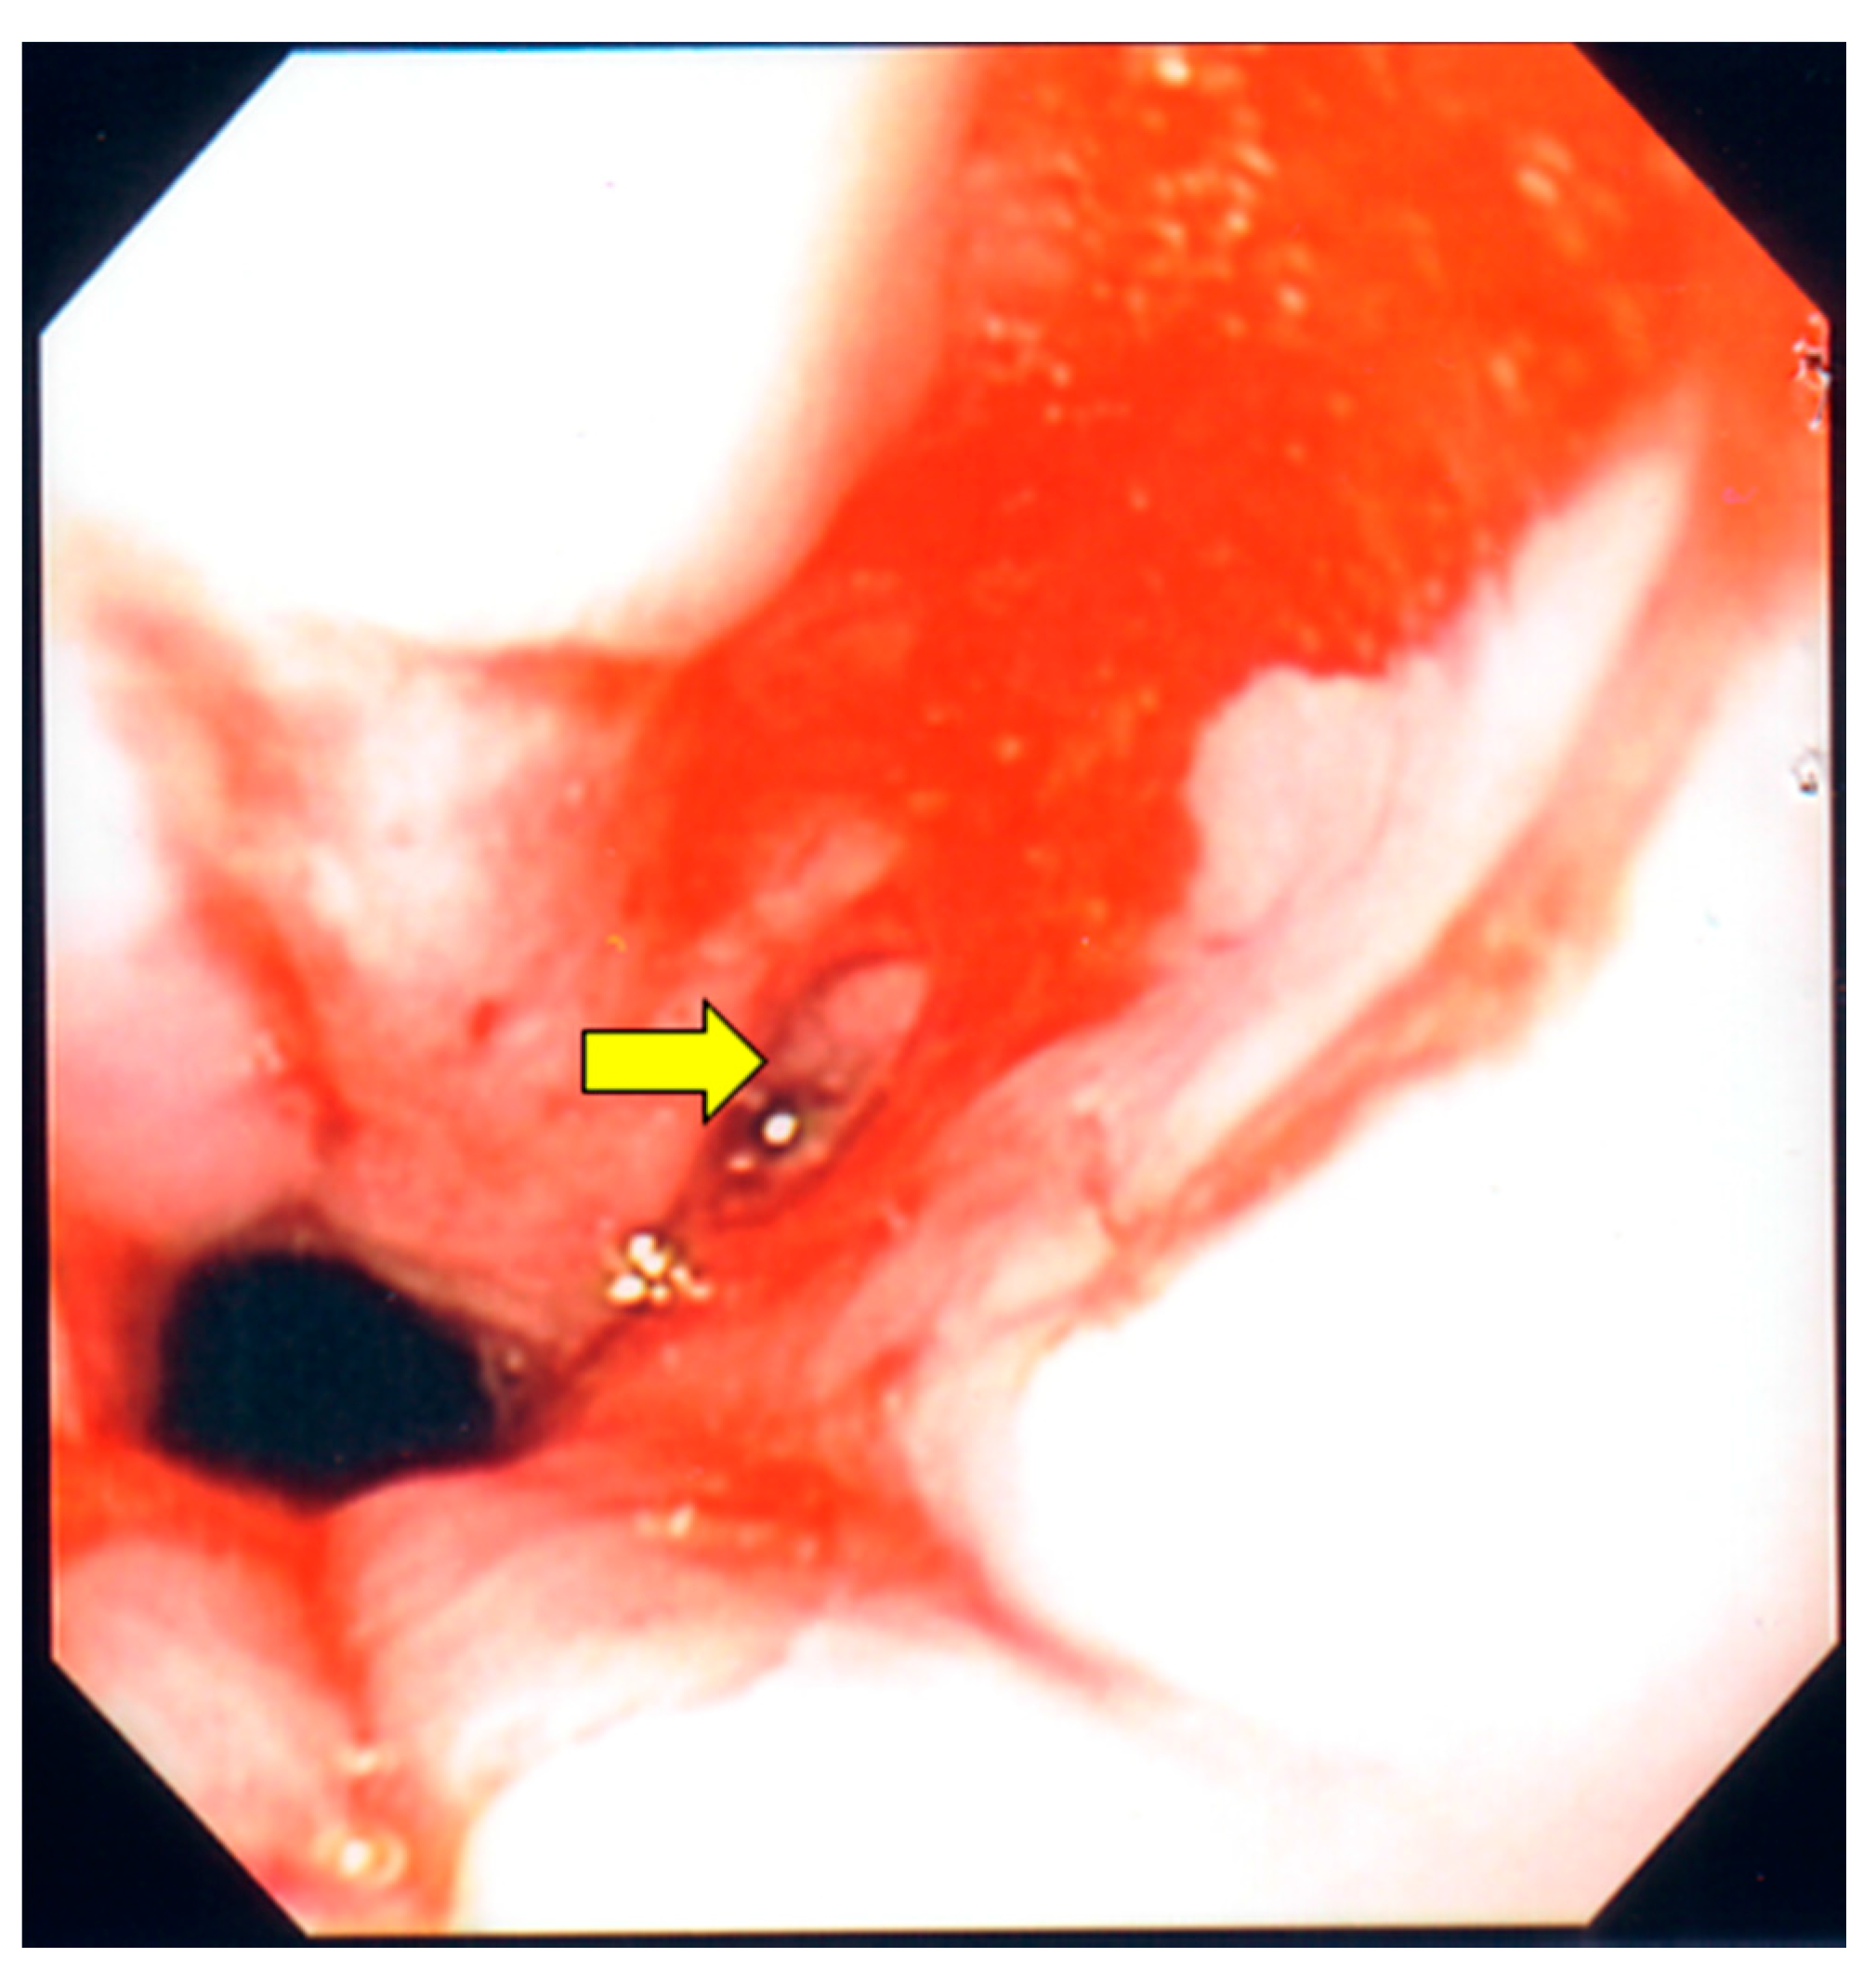

Figure 2.

Upper endoscopy. The yellow arrow points to an ulceration found in the mid portion of the esophagus, which was secondary to cytomegalovirus esophagitis.